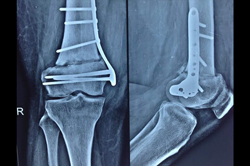

Proximal Tibia